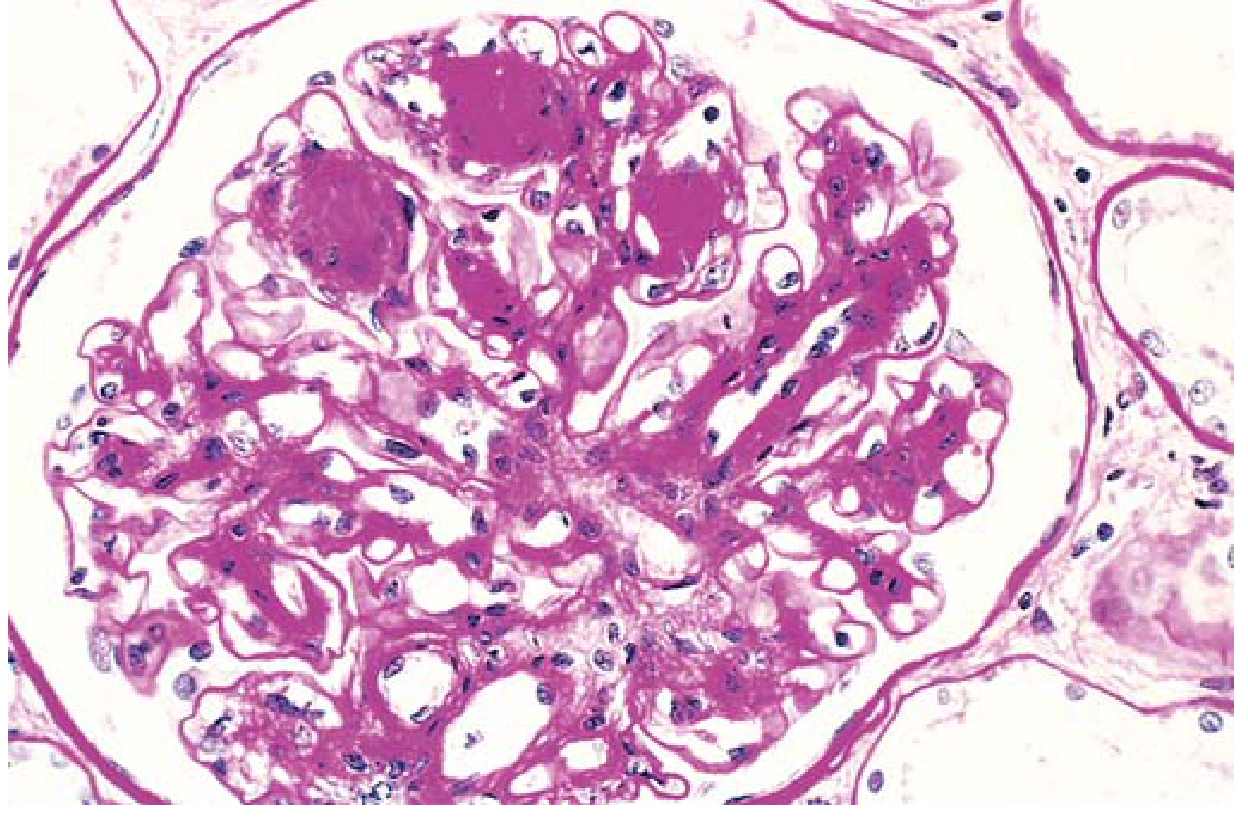

1. Glomerular lesions: Diffuse glomerulosclerosis (most common — diffuse increase in mesangial matrix); nodular glomerulosclerosis (Kimmelstiel-Wilson nodules) — ovoid PAS-positive deposits in the mesangium, pathognomonic of diabetic nephropathy

Nodular glomerulosclerosis (Kimmelstiel-Wilson nodules) in diabetic nephropathy — PAS stain, Robbins Basic Pathology

Diabetic nephropathy — nodular glomerulosclerosis. PAS stain shows Kimmelstiel-Wilson nodules (ovoid mesangial deposits). — Robbins & Kumar Basic Pathology